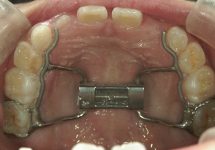

急速拡大装置(きゅうそくかくだいそうち)

2週間かけて、上顎の骨のつなぎ目を急速に広げる装置です。1日2回、中央についている拡大調節ネジを調整することで、強い力で歯列を押し広げます。永久歯に生えそろってから、あまり時間のたっていない20歳くらいまで効果がみられます。